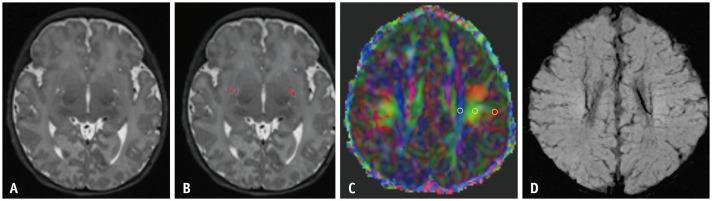

MATERIALS AND METHODS

This retrospective, single-institution study collected brain MRI scans of 127 neonates between July 2020 and July 2022. The volume and fraction of the basal ganglia perivascular space (BG-PVS) were automatically extracted using three-dimensional T2-weighted image processing. Diffusion-tensor imaging (DTI) along the PVS (DTI-ALPS) index values were derived from the DTI maps. BG-PVS and DTI-ALPS parameters were compared between neonates with and without HII. The correlations between MRI-derived glymphatic parameters and corrected gestational age (CGA), as well as between BG-PVS measurements and the DTI-ALPS index, were analyzed using Spearman coefficients. Multivariable logistic regression adjusted for age, sex, birth weight, and mode of delivery was performed to examine the associations between each glymphatic parameter and HII.

材料与方法

这项回顾性单机构研究收集了2020年7月至2022年7月期间127例新生儿的脑部MRI扫描图像。使用三维T2加权图像处理自动提取基底节周围血管间隙(BG-PVS)的体积和分数。沿PVS的扩散张量成像(DTI)(DTI-ALPS)指数值由DTI图得出。比较有和没有HII的新生儿之间的BG-PVS和DTI-ALPS参数。使用Spearman系数分析MRI衍生的类淋巴参数与校正胎龄(CGA)之间的相关性,以及BG-PVS测量值与DTI-ALPS指数之间的相关性。进行了针对年龄、性别、出生体重和分娩方式调整的多变量逻辑回归分析,以检验每个类淋巴参数与HII之间的关联。